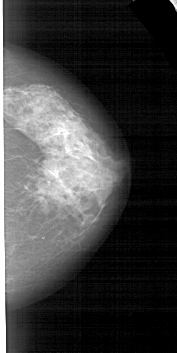

A_1553_1.LEFT_MLO

LEFT_MLO LINES 5491 PIXELS_PER_LINE 2776 BITS_PER_PIXEL 12 RESOLUTION 43.5 OVERLAY